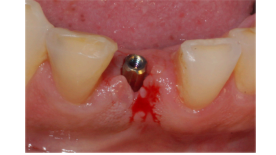

Após os três meses, foi realizada a abertura do implante e foi instalado um cicatrizador, que permaneceu no local por dez minutos para manter os tecidos afastados.

Após esse período, foi selecionado o pilar, e um Pilar Ideale reto de 3.3 X 4.0 X 1.5 mm foi instalado e torqueado a 20 Ncm (Figuras 13 e 14).